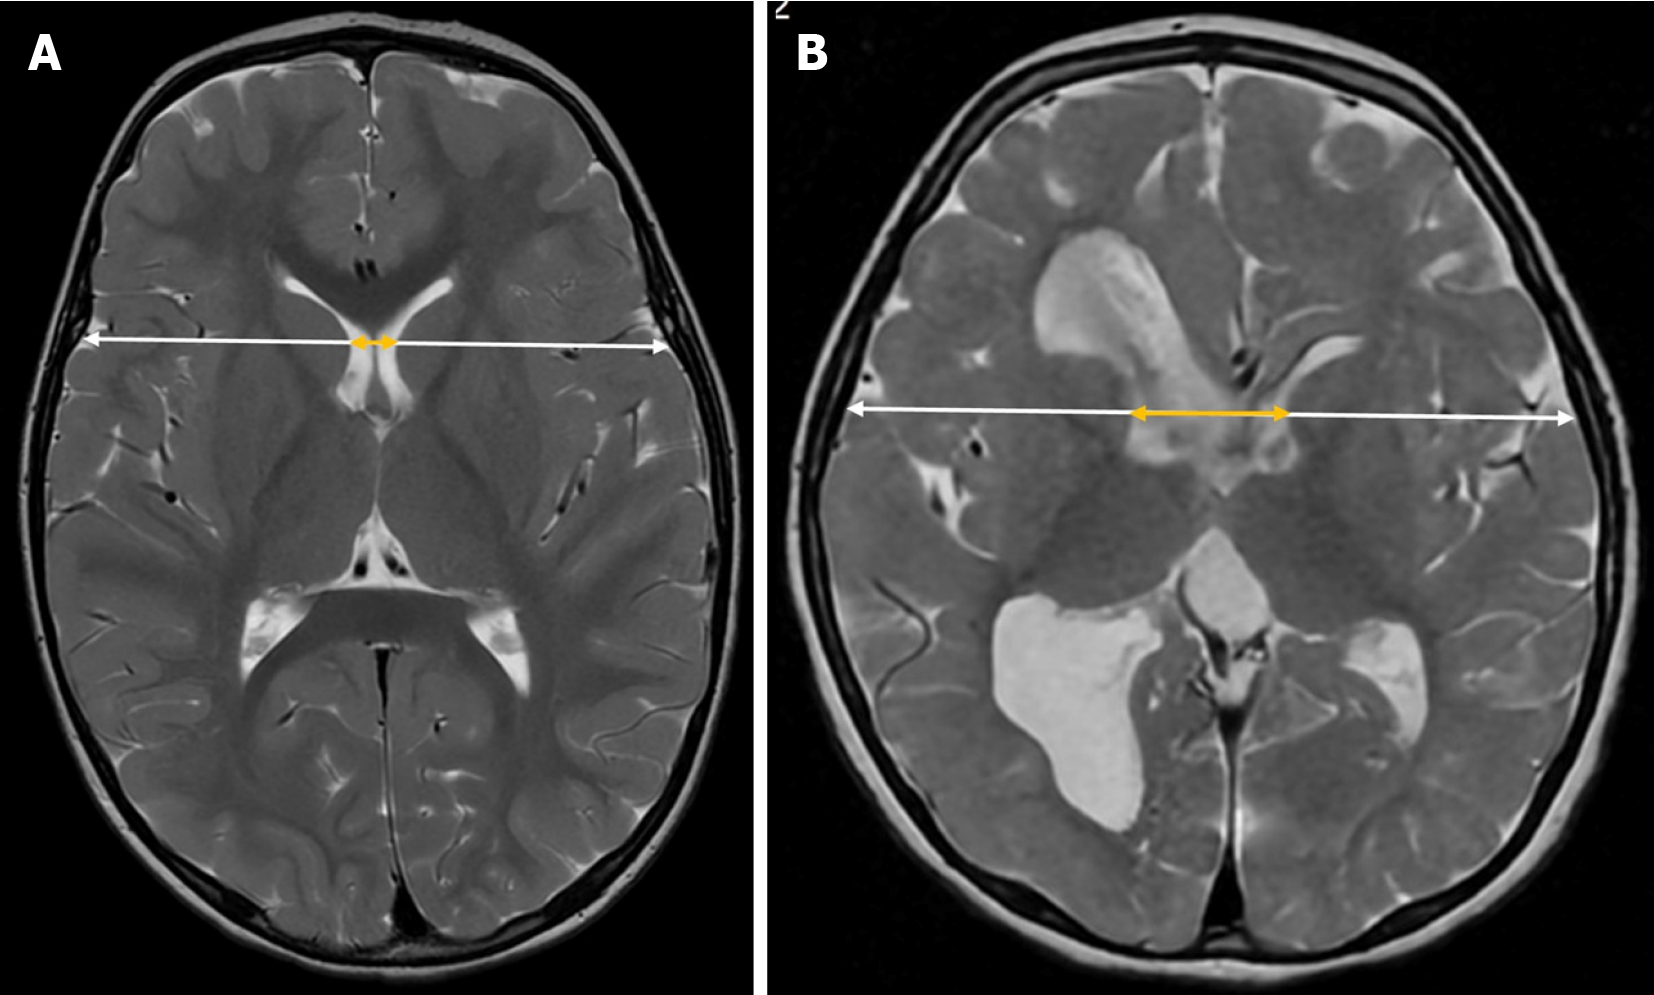

The Cella media index is a neuroimaging tool used in neuroradiology to assess the size of the lateral ventricles relative to brain tissue. It is calculated by dividing the biparietal diameter of the skull by the maximum external diameter of the central portions of the lateral ventricles (Cella media) (Figure 5).

A Cella media index greater than 4 is generally considered normal, while lower values may suggest ventricular dilation. Although reference values for the Cella media index are generally considered stable[28,29], studies have reported variations across different age groups[30]. Additionally, its correlation with third ventricle size supports its reliability as a biomarker for ventricular dilation[29].

The Bicaudate index is a neuroimaging tool used to assess the size of the frontal horns of the lateral ventricles in relation to the transverse diameter of the brain. To calculate this index, the distance between the most lateral portions of the frontal horns of the lateral ventricles at the level of the caudate nuclei is measured and then divided by the transverse brain diameter at the same level (along the same reference line used for ventricular measurements) in the axial plane on CT or MRI[33] (Figure 7).

There are no standardized reference values for this index. As with other ventricular indices, its application in transfontanellar ultrasound is technically challenging, limiting its use primarily to CT and MRI. Moreover, since it assumes ventricular symmetry, its diagnostic reliability decreases in cases of asymmetry or congenital ventricular malformations.